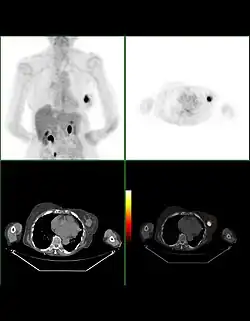

Beim PET/CT wird der Patient unmittelbar hintereinander durch beide Detektorringe (Gantries) von CT und PET gefahren. Da der CT-Datensatz für die Rekonstruktion der PET-Daten benötigt wird, wird in der Regel zunächst eine CT-Aufnahme durchgeführt und die PET-Aufnahme daran angeschlossen. So kann bereits nach Beendigung der Aufnahme der ersten Bettposition mit der Bildrekonstruktion begonnen werden. Würde zunächst der PET-Datensatz aufgenommen, müsste mit dem Beginn der Bildrekonstruktion der PET-Daten gewartet werden, bis der CT-Datensatz rekonstruiert ist und zu unerwünschten Verzögerungen im Arbeitsablauf führen, denn die Rekonstruktion eines Ganzkörper-PET-Datensatzes benötigt je nach Gerät und Rechenmethode ca. 10–45 Minuten Zeit. Eine laufende CT-Aufnahme ist für den Patienten daran erkennbar, dass der Tisch bewegt wird, während gleichzeitig ein Motorengeräusch hörbar ist, das in erster Linie von der Rotationsbewegung von Röhre und Detektorsystem stammt. Die Gantries sind bei einigen Systemen im selben Gehäuse untergebracht und nicht einzeln von außen sichtbar. Die errechneten Bilder werden im Computer automatisch fusioniert.

Bei PET/CT-Geräten ist die CT-Aufnahme für die Berechnung schwächungskorrigierter PET-Bilder zwingend erforderlich, jedoch reicht ein so genannter Low-Dose-CT-Scan hierfür aus. Bei einigen Geräten kann für die Errechnung der Schwächungsmap jedes CT-Protokoll, also auch eine diagnostische CT-Aufnahme genutzt werden; einige Geräte fordern zwingend die zusätzliche Durchführung eines dedizierten Low-Dose-Scans, selbst wenn vom Patienten bereits eine Hoch-Dosis-CT-Aufnahme existiert.

Befundung

Die Befundung des PET- oder PET/CT-Bildes erfolgt durch Betrachtung der rekonstruierten Schnittbilder (axial, koronar oder sagittal). Bei PET/CT-Geräten ist die Darstellung von PET und CT verknüpft, so dass automatisch die Position des korrelierenden PET-Bildes gezeigt wird, wenn der Bildkursor im CT-Bild verschoben wird.

Für eine Übersichtsdarstellung wird ein sogenanntes MIP-Bild (Maximum Intensity Projection) herangezogen. In dieser Darstellung ist das gesamte Untersuchungsobjekt abgebildet und man erlangt einen schnellen Überblick über Regionen erhöhter Aufnahme. Zur nochmals besseren Visualisierung kann man das MIP um sich selbst rotieren lassen, um das Untersuchungsobjekt von allen Seiten zu zeigen.